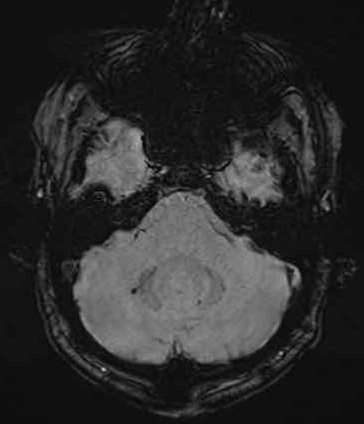

下图 一位46岁的男子骑摩托车时受伤。

瞳孔无反应性,瞳孔扩张。

CT:额叶点状出血。

继续做核磁共振成像

弥漫性轴索损伤(DAI)MRI表现

- 累及皮质下区、胼胝体、右侧丘脑和壳核、脑干、小脑脚和右侧小脑半球。

- 轻度全球萎缩。

MRI可准确诊断DAI,包括T2*GRE或SWI。

DAI在颅脑损伤患者MRI上的存在,更有可能导致不良的功能结局。